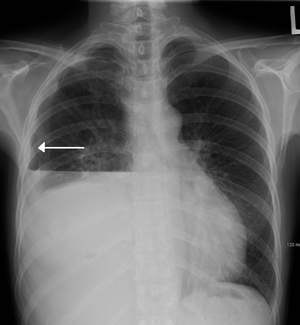

| A hydropneumothorax with white arrow point to the lung's pleura | |

Hydropneumothorax is defined as the presence of both air and fluid within the pleural space surrounding the lung. An upright chest x-ray will show air fluid levels. The horizontal fluid level is usually well defined and extends across the whole length of hemithorax.